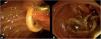

Ascaris lumbricoides is a soil-based helminth parasite. It is distributed worldwide, with a high incidence in tropical regions, including those of Colombia and Mexico. Infection with the parasite is considered a neglected tropical disease. Diagnosis is made through microscopic observation of the parasite’s eggs or macroscopic identification of the parasitic worm, such as during endoscopy. A 56-year-old woman, with a past history of cholecystectomy, arrived at the emergency department with diffuse colicky abdominal pain, located in the right hypochondrium, and choluria, for the past 24 h. She also presented with generalized jaundice, leukocytosis, direct hyperbilirubinemia, and elevated transaminase and alkaline phosphatase levels. Magnetic resonance cholangiopancreatography (MRCP) showed the absence of the gallbladder, a metallic clip in the cystic duct, choledocholithiasis, and dilatations of the intrahepatic and extrahepatic bile ducts of 15 and 13 mm, respectively (Fig. 1). Cholangitis was initially considered, and ampicillin-sulbactam was started. A scheduled endoscopic retrograde cholangiopancreatography (ERCP) revealed extrahepatic dilatation and a 12 × 15 mm stone in the common bile duct. Lithotripsy was performed, and an adult Ascaris lumbricoides was discovered and extracted (Video 1 and Fig. 2A and B). Treatment with a single dose of 400 mg of albendazole was indicated. After clinical improvement, the patient was discharged to her home. She had no recurrence during follow-up. Treatment options include albendazole, ivermectin, and nitazoxanide, and in some cases, endoscopic extraction.